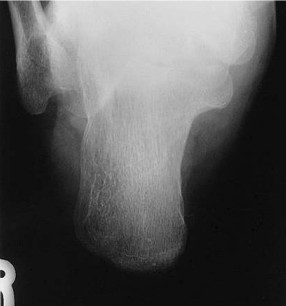

What is the correct centering point for this calcaneus projection?

1 inch (2.5 cm) inferior to medial malleolus

Should the foot be dorsiflexed or left in a neutral position for this mediolateral calcaneus projection?

Dorsiflex foot

What anatomy is correctly demonstrated on this lateral calcaneus

calcaneus demonstrated in profile with talus and distal tibfib demonstrated superior and navicular and open joint space of the calcaneus and cuboid demonstrated distally

On this lateral calcaneus image, what indicates no rotation?

superimposed superior parts of the talus, open talocalcaneal joint, lateral malleolus superimposed over posterior half of the tibia and talus. Tarsal sinus and calcaneocuboid joint space should appear open